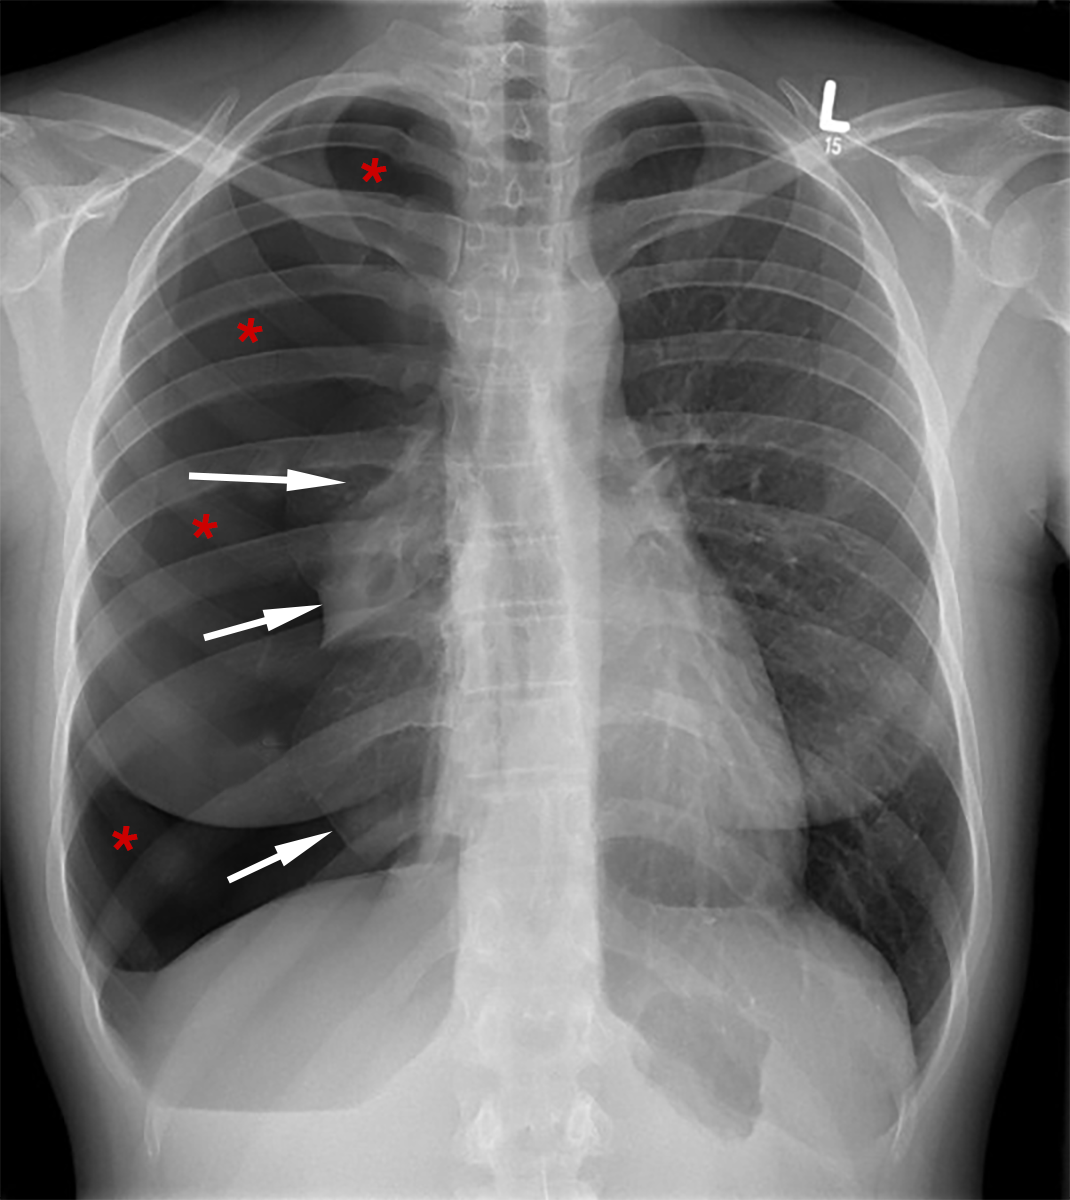

![]() |

| Abb. 6 |

| Verdickung der Wand des linken Ventrikels mit unnatürlich hohen R-Zacken (rote Pfeile) und Senkungen der ST-T-Strecke (schwarze Pfeile) bei Herzmuskelkrankheit |

Im Röntgenbild des Brustkorbes kann man u.U. Hinweise auf eine Erkrankung des Herzens sehen, wie z.B. Vergrößerungen und Verdickungen des linken Ventrikels, jedoch sind diese Röntgenhinweise im allgemeinen nicht sehr aussagekräftig.

Das Röntgenbild ist aber dennoch wichtig, denn es zeigt auch Erkrankungen der Lungen, wie z.B. einen Pneumothorax (Luftansammlung im Spalt zwischen Lungen- und Brustfell), bei dem ein Teil der Lungen zusammenfällt (Abb. 6).

U.U. kann man aber auch die Zeichen einer Lungenentzündung, einer Flüssigkeitsansammlung im Brustkorb (Pleuraerguß) oder auch Tumore sehen.